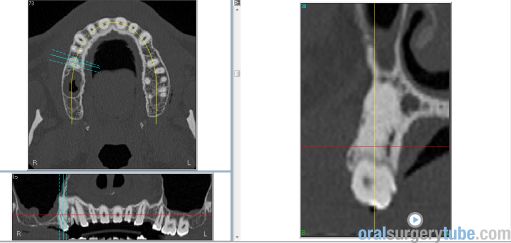

A fecha de hoy, 02.04.2020 y con un poco de retraso, actualizamos el post de este caso que ya está concluido y por suerte, tuvimos un final feliz.  Tras haber dado por resuelto el proceso infeccioso en fecha 02.10.2018 (4 meses después de la Elevacion de Seno), en fecha 27.03.2019 colocamos los implantes.  Espacíficamente colocamos tres implantes Paltop Dynamic en posiciones 1.4, 1.6 y 1.7. 18.09.2019 Segunda cirugía y 2.01.2020 la prótesis.

A fecha de hoy, 02.04.2020 y con un poco de retraso, actualizamos el post de este caso que ya está concluido y por suerte, tuvimos un final feliz. Tras haber dado por resuelto el proceso infeccioso en fecha 02.10.2018 (4 meses después de la Elevacion de Seno), en fecha 27.03.2019 colocamos los implantes. Específicamente colocamos tres implantes Paltop Dynamic en posiciones 1.4, 1.6 y 1.7. En fecha 18.09.2019 realizamos la segunda cirugía y en fecha 02.01.2020 iniciamos las prótesis y las concluimos en fecha 24.02.2020. Lo más relevante de este caso fue el finalmente encontrar la posible causa del proceso infeccioso tras la elevación de seno. Este paciente padece una artritis psoriásica y estaba siendo tratado con metotrexato (cosa que desconocíamos), fármaco que provoca inmunodepresión. Tras la infección aguda, fue tratado con Actira 400 y Trigon Depot, y con ello se consiguó doblegar la infeccion.